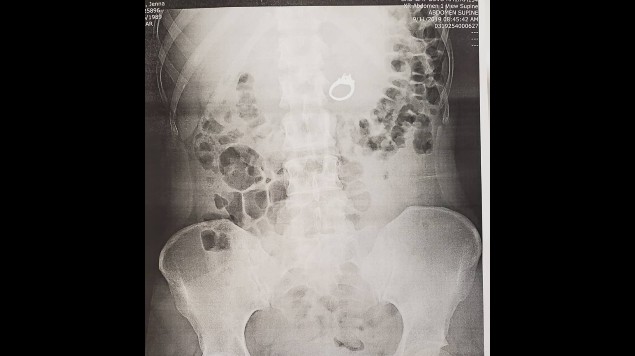

Los especialistas detectaron que efectivamente se lo tragó. Rápidamente descartaron la opción de esperar a que el anillo saliera por vía natural y remitieron a la paciente al servicio de gastroenterología, donde le practicaron una endoscopia superior y recuperaron el anillo